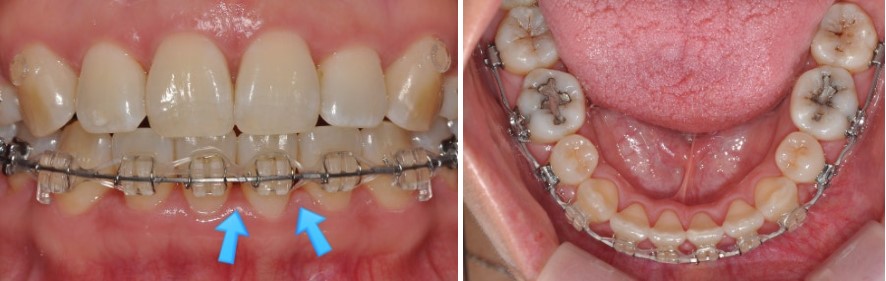

예를 들어,

돌출과 치아 배열 때문에 내원하신 30대 여성 환자분의 경우,

이때 치간삭제를 시행하고 공간을 다시 닫아 주면서

블랙 트라이앵글이 완전히 사라지지는 않더라도

눈에 띄게 크기가 줄고, 치아 사이가 더 긴밀하게 붙어 보이는 효과를 얻을 수 있습니다.

실제 환자 케이스로 보는 치간삭제 활용